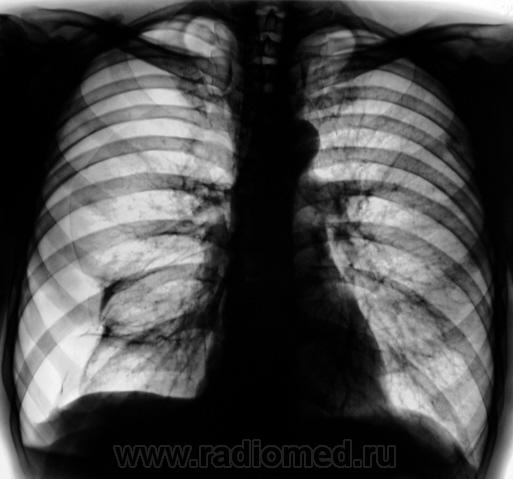

Пневмоторакс справа Если жалоб нет, совсем нет...Зачем делали рентгенограмму

Пациент пришел на флюшку (профилактическую), флюшку сделали, прибежал лаборант с флюорографа, попросил посмотреть. Посмотрел, забрал в рентген-кабинет, сделали стандарт - прямо и боком...